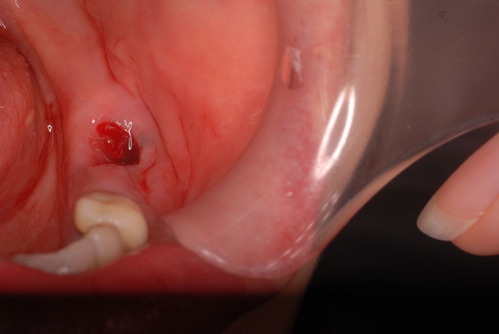

写真は典型的な取り残したまま銀歯を入れていた方のものです。よくぞ痛くならなかったものです。

意外と手間取り一時間以上かかりセメントを入れてとりあえず終了いたしました。神経が近いので傷つけて損傷すると助かる見込みが少なくなり、痛みが出て死んでしまうとか膿んでしまうこともあるのです。![570b1c06-s[1]](https://livedoor.blogimg.jp/netdental/imgs/6/0/60221eb2.jpg)